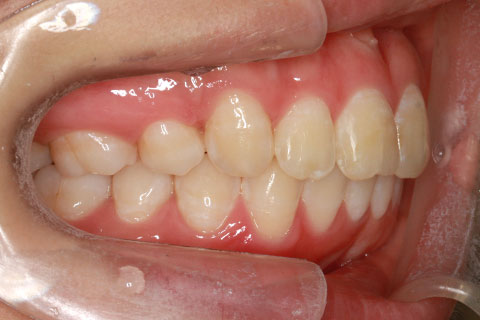

フルリンガル矯正2:上下の歯を舌側矯正で治療(矯正期間18ヶ月)

- 年齢・性別

- 42歳男性

- 治療期間

- 1年6ヶ月

- 抜歯

- なし

- 治療費

- 120万円(税込み)

- 備考

- マルチブラケットを用いた矯正治療

- 治療内容

- 反対咬合をフルリンガル矯正治療にて改善

- 施術の副作用(リスク)

- 表側矯正と比較して、歯根の角度を確立する「トルク」の力がかかりにくい。